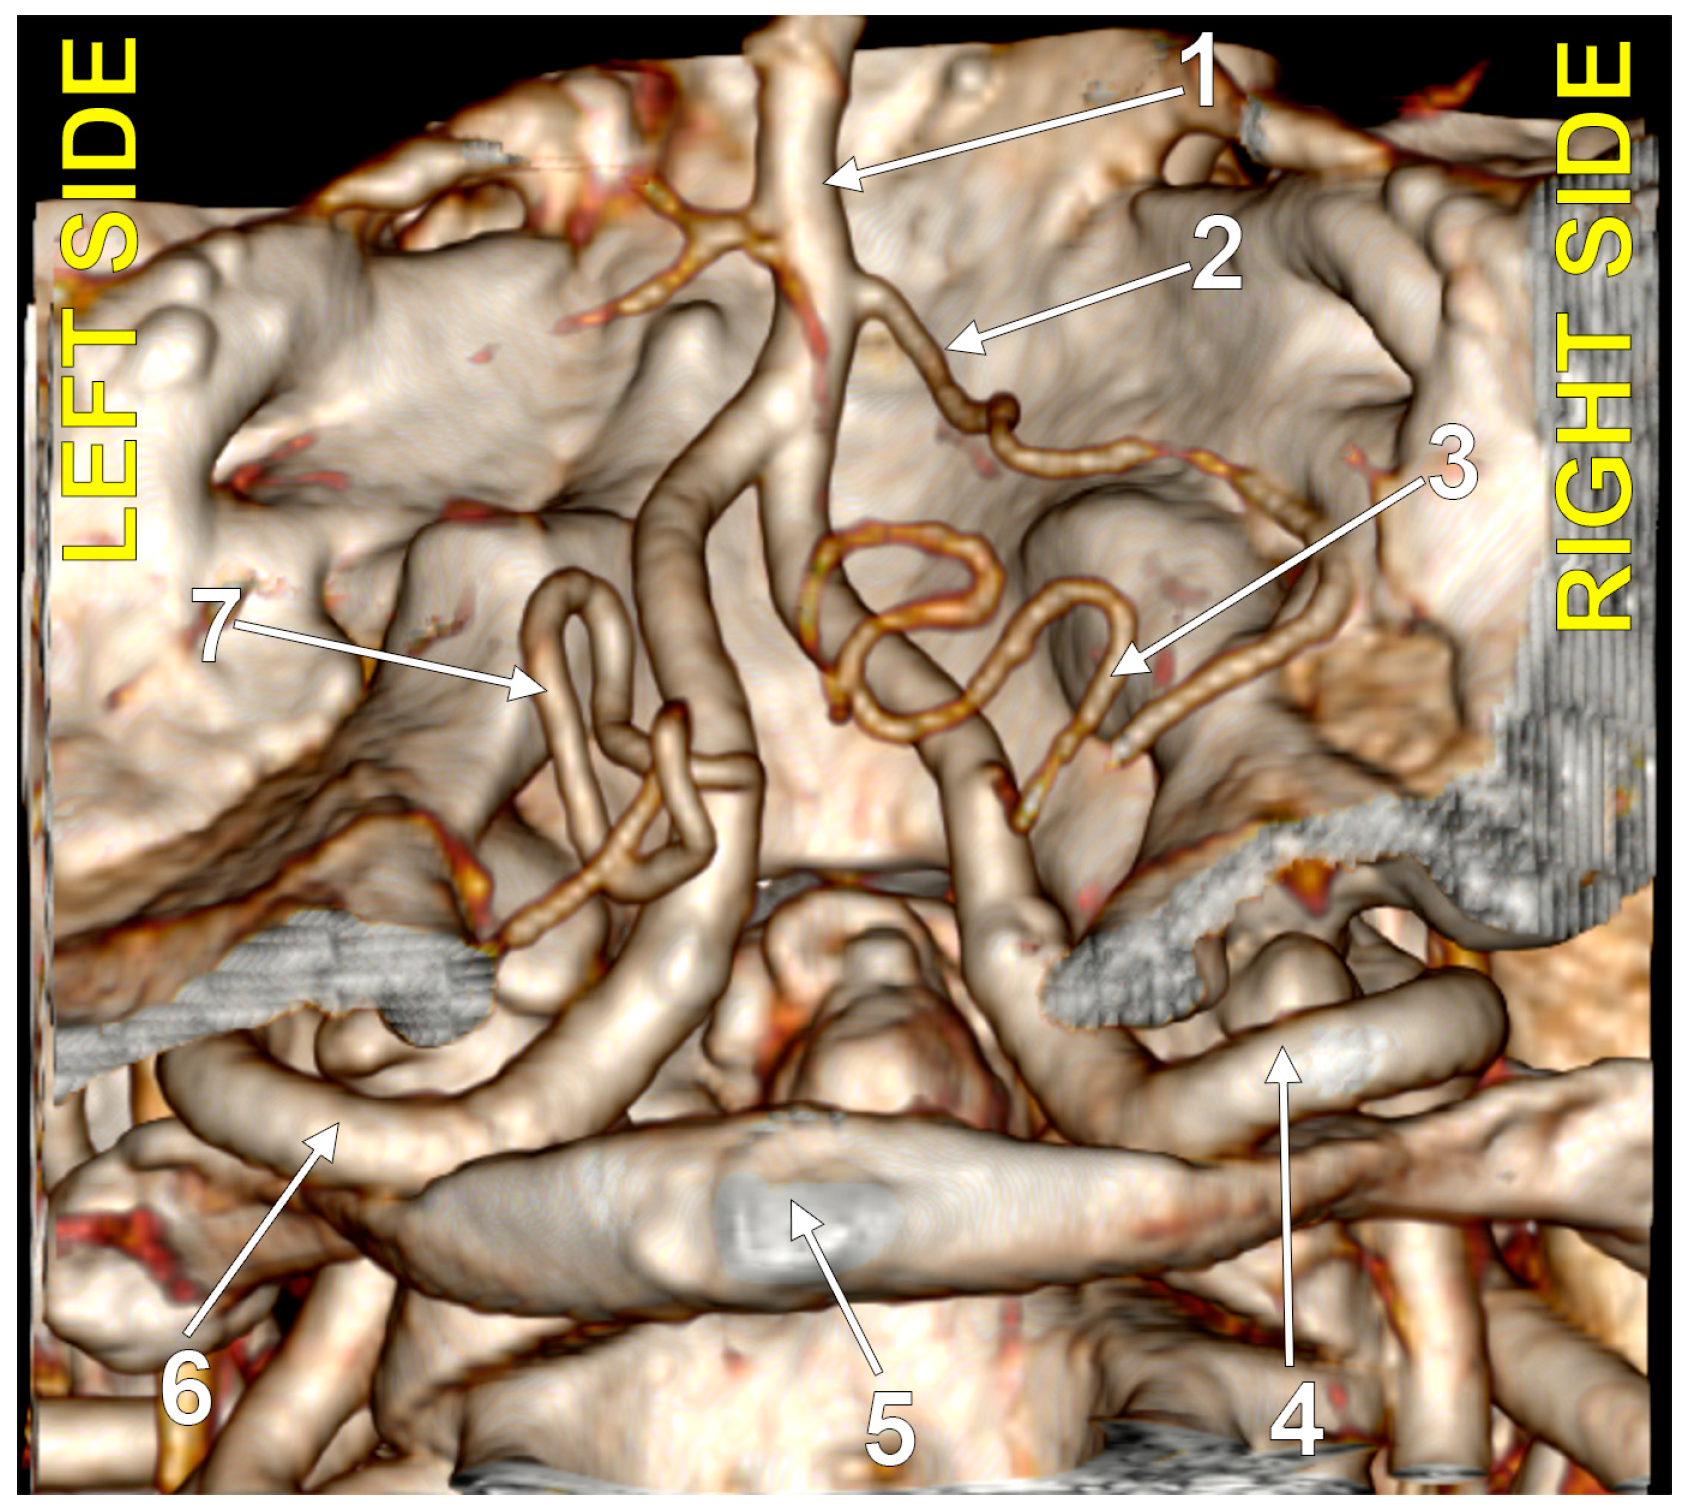

4.8. The Caudal Loop of the PICA